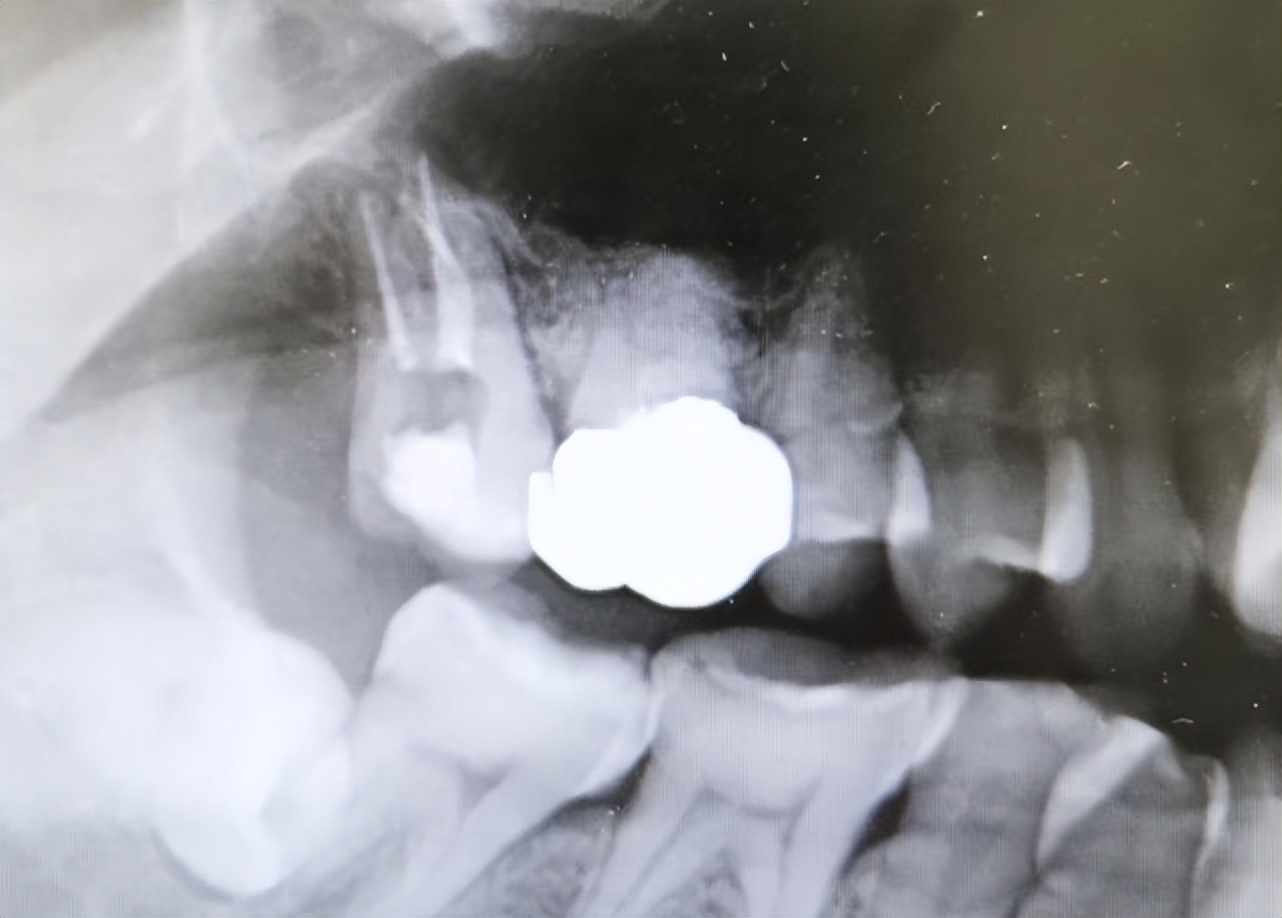

初步考虑患者为17慢性牙髓炎后,为了进一步明确诊断,建议患者进行了x线片检查,检查结果提示:17冠部低密度影近髓腔,根管内无填充物影,根尖区无低密度影。

基于上述检查结果,我考虑患者存在牙髓病变,结合患者的症状以及查体表现,诊断为“17慢性牙髓炎”,明确了患者的诊断后,我决定对患者进行17根管治疗+冠修复。具体操作如下:17去腐未净露髓,3%Naclo冲洗,放置Antipulp失活剂,玻璃离子暂封。